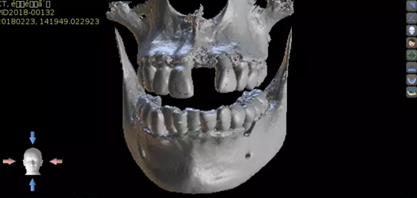

1.術(shù)前CT

2.術(shù)前植體設(shè)計(jì)

3.術(shù)前導(dǎo)板設(shè)計(jì)

術(shù)后CT